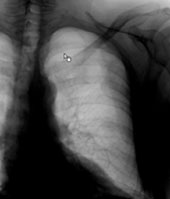

Ein 42-jähriger Freizeitsportler stürzte vor einigen Tagen bei einer Velotour auf die linke Flanke und kommt nun in Ihre Praxis wegen persistierenden thorakalen Schmerzen, v.a. bei tiefer Inspiration.

Sie veranlassen ein Thoraxröntgen, dessen Aufnahmen Sie hier sehen:

Thorax (Ausschnittsaufnahme)

Bild vergrössern